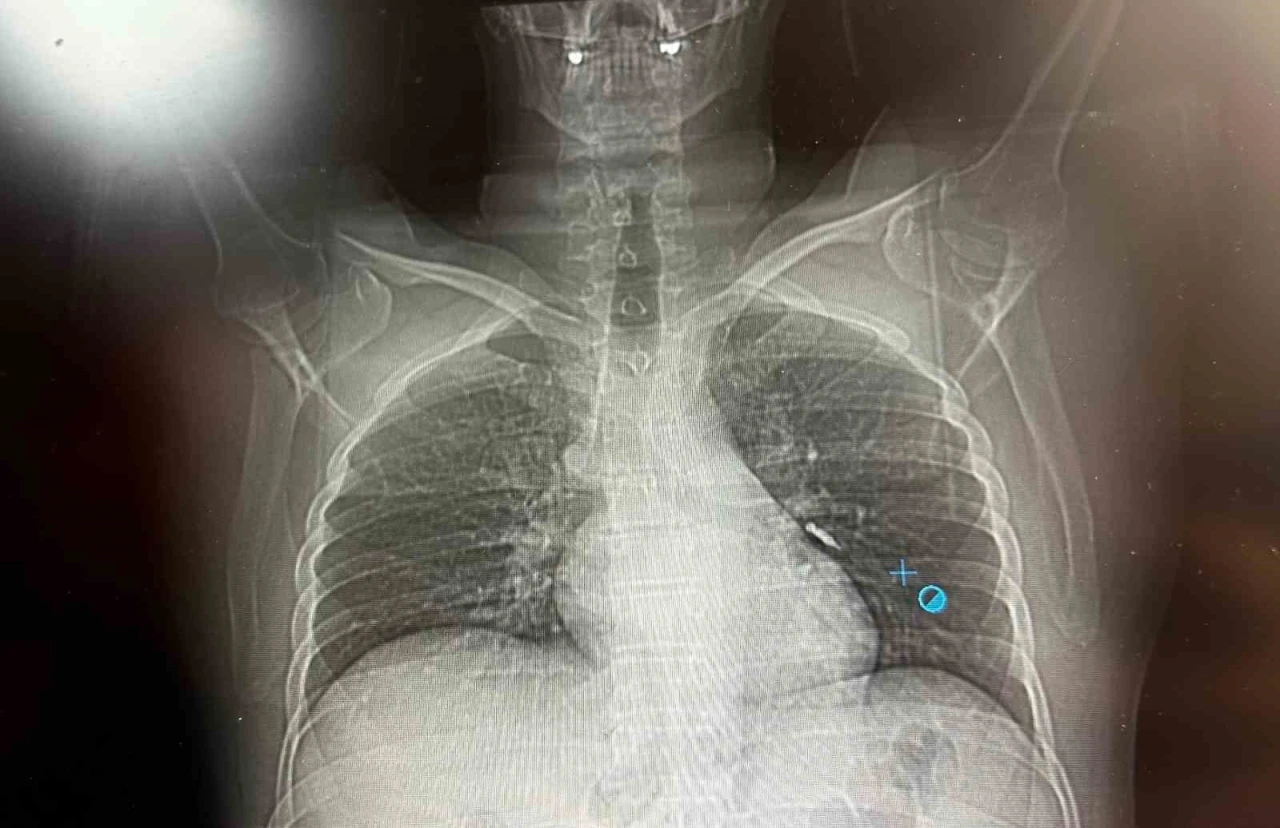

Konuya ilişkin konuşan Göğüs Cerrahi Op. Dr. Sadullah Aksoy, bir diş merkezinde diş tedavisi sırasında hastanın çenesine yerleştirilen implantın vida kısmının işlem esnasında yanlışlıkla aspire edildiğini belirtti. İlk olarak hastanenin ek hizmet binasında çekilen tomografi sonucunda, vidanın sol akciğerin hava yollarının yaklaşık dördüncü dalına kadar ilerlediği tespit edildiğini ifade eden Op. Dr. Aksoy, "Geçtiğimiz cumartesi günü öğle saatlerinde tarafımıza ulaşıldığında, hastanın Van Eğitim ve Araştırma Hastanesi’ne yönlendirilmesini istedik. Burada acil bronkoskopi planı yapılarak hasta kabul edildi. Hasta geldiğinde genel durumu iyiydi; solunumunu tamamen engelleyen bir bronş tıkanıklığı söz konusu değildi. Aynı gün hastamızı hazırladık. Bronkoskopi sırasında, implant vidasının sol üst lobun anterior segment bronşuna saplanmış pozisyonda olduğunu gördük. Üroloji bölümünde taş çıkarma işlemlerinde kullanılan cihazla müdahale ettik. İlk denemede implant tamamen çıkarılamadı ancak yerinden oynatılabildi. Bunun üzerine bir süre bekleyip hastayı yeniden bronkoskopi için hazırlamaya başladık. İşlem yaklaşık 3,5-4 saat sürdü ve saat 18.30 civarında hasta işlemden çıkarıldı" dedi. "İmplant vidası öksürük sonrası akciğerden çıktı"

Daha sonra hasta için yeniden bronkoskopi planladıklarını ancak bu süreçte hasta şiddetli bir öksürük geçirdiğini anlatan Aksoy, "Şiddetli öksürük sonrası yapılan kontrol akciğer filminde implant vidası görünmedi. Bunun üzerine toraks ve batın BT (bilgisayarlı tomografi) görüntülemesi istedik. Sonuçlarda implantın akciğerden çıktığı ve vücutta herhangi bir yerde bulunmadığı tespit edildi" diye konuştu. "İyileşme süreci sorunsuz tamamlandı"